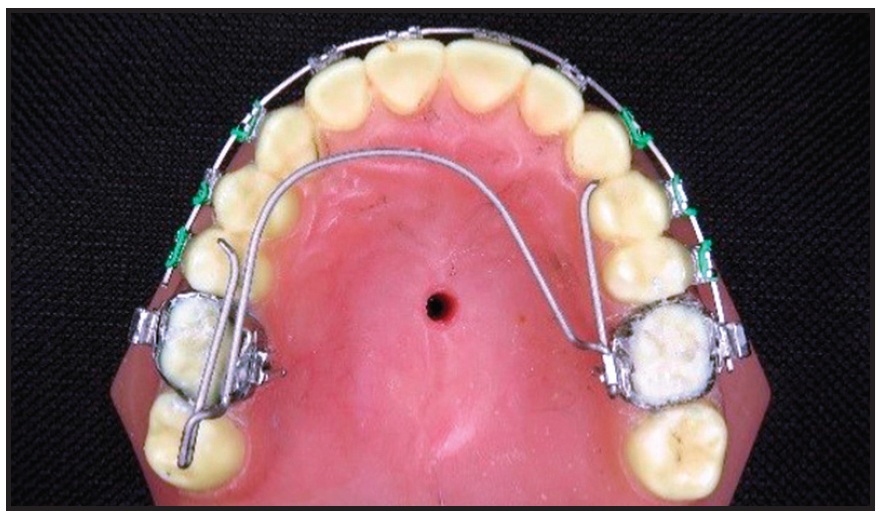

Fig. 2 Construction of non-helix appliance.